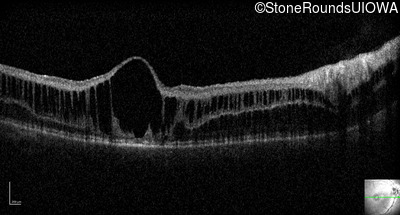

Optical Coherence Tomography - Left - 10/40

Exemplar / OCT Stack